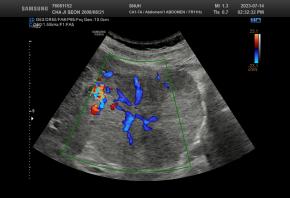

Elastography for the differential diagnosis of malignant versus benign testicular lesions: a meta-analysis

Ziwei Lin, Rui Lin, Huaiyu Wu, Linghu Wu, Jieying Zeng, Jinfeng Xu, Fajin Dong